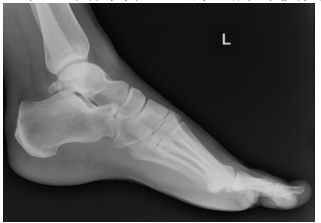

53 一位芭蕾舞者,主訴左腳踝後側疼痛,無跌倒扭傷病史,X 光如下圖。下列處置敘述何者最適當? (A)為距骨後突骨折,需徒手復位,夾板固定 (B)照右側 X 光比較 (C)為距骨後突骨折,需手術內固定復位,以預防缺血性壞死 (D)為距骨後突骨折,需復位石膏固定,以預防缺血性壞死